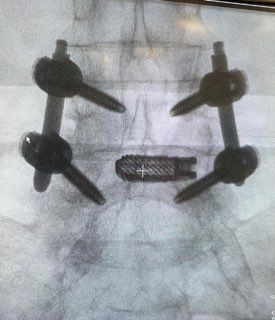

Starszy Asystent w Klinicznym Oddziale Neurochirurgicznym oraz Poradni Neurochirurgii Wojewódzkiego Szpitala Specjalistycznego im. św. Barbary nr 5 w Sosnowcu. Konsultant Kliniki Neurologii Szpitala Klinicznego nr 1 w Zabrzu. Absolwent Wydziału Lekarskiego Śląskiego Uniwersytetu Medycznego w Zabrzu. Staż podyplomowy odbył w latach 2010-2011 w Oddziale Neurochirurgii WSS nr 4 w Bytomiu. W 2018r. złożył egzamin specjalizacyjny po zakończeniu szkolenia w ramach rezydentury w WCM Opole. W 2019 roku uzyskał stopień doktora nauk medycznych. Specjalizuje się w kompleksowym leczeniu schorzeń kręgosłupa (dyskopatia, stenoza kanału kręgowego, kręgozmyk) oraz neuroonkologii. Szczególny zakres działań medycznych to nowoczesne, małoinwazyjne operacje kręgosłupa z wykorzystaniem technik endoskopowych (mikrodiscektomia - implanty rozprężalne), przezskórnych stabilizacji oraz mikrochirurgicznych dekompresji. Wykonuje procedury iniekcyjne; discoGEL, GelSTIX, kriolezje oraz blokady przeciwbólowe kręgosłupa odcinka szyjnego, lędźwiowo-krzyżowego a także stawów krzyżowo-biodrowych, które odgrywają istotną rolę w procesie diagnostyczno-leczniczym wielu zespołów bólowych. Na co dzień przeprowadza operacje w ramach kontraktu z NFZ. Członek Polskiego Towarzystwa Neurochirurgów oraz Polskiego Towarzystwa Chirurgii Kręgosłupa. Uczestnik wielu krajowych i zagranicznych kursów neurochirurgicznych, m.in. w Czechach, Słowacji, Niemczech, Włoszech, Danii, Austrii, Szwajcarii i USA. Autor licznych publikacji naukowych.

Zdjęcia i filmy